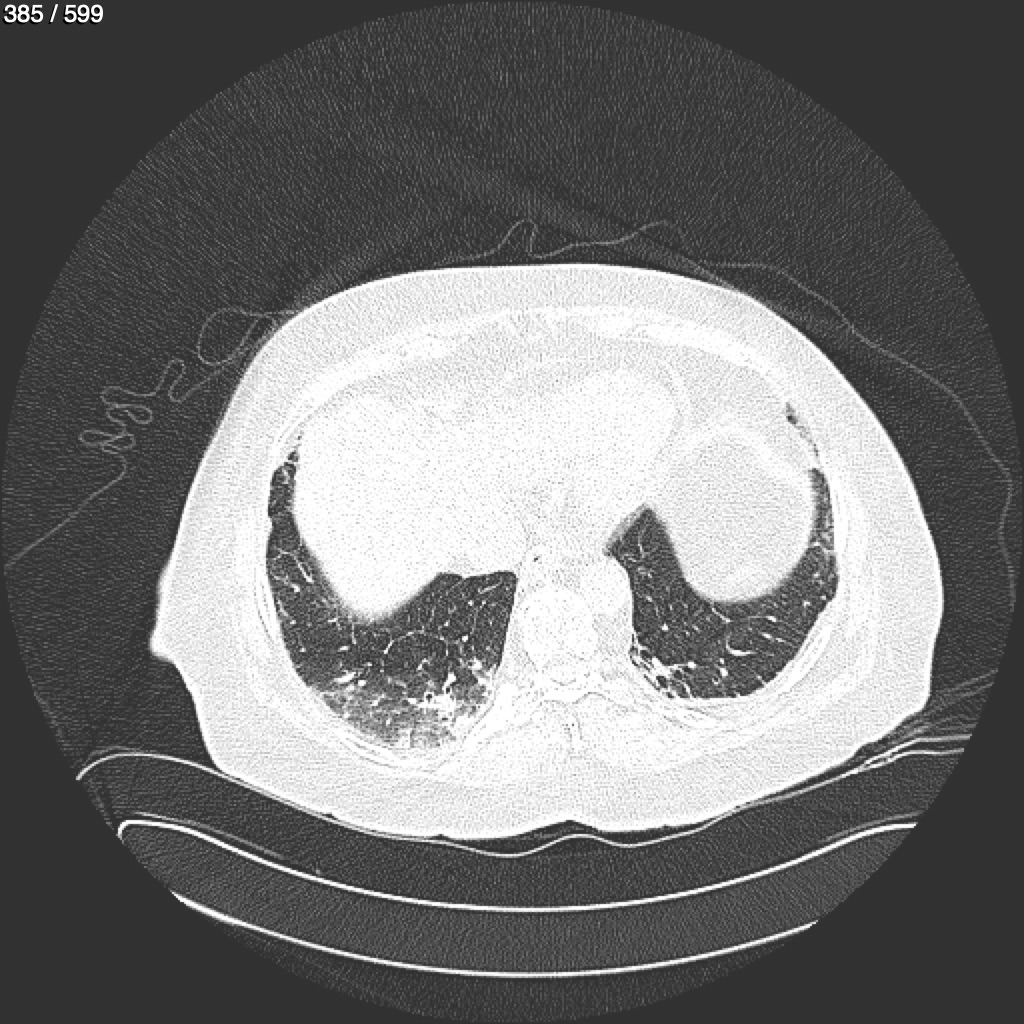

Home G​l​o​r​i​a​ ​G​l​a​d​y​s​ ​B​e​a​s​l​e​y​ ​-​ ​T​ó​r​a​x​ ​T​o​r​a​x​_​S​i​m​p​l​e​ ​(​A​d​u​l​t​o​)